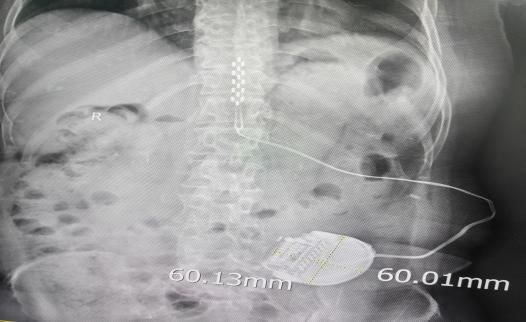

神经外科王举波副主任医师汇报了一例脊髓电刺激术治疗糖尿病痛性周围神经病患者的情况。患者是一名患糖尿病十余年的中年女性,3年前出现左侧小腿皮肤溃烂,反复换药仍难以愈合,1年前开始出现双下肢持续性疼痛并日益严重,剧痛导致夜不能寐,长期失眠,药物治疗无效,在外院接受双下肢血管介入治疗效果亦不佳,遂来我院就诊,以“糖尿病痛性周围神经病”之诊断收住院。入院时双下肢皮肤温度低,紫绀,左侧小腿皮肤溃疡直径约9cm,双下肢温度觉、触觉均减退,神经电生理检查显示“双下肢周围神经病损,感觉、运动均受累”,CTA检查见双下肢动脉广泛重度狭窄,踝肱指数极低,疼痛VAS评分达10分(VAS是一种评估疼痛强度的临床工具,将疼痛程度由轻到重计为0分﹝完全无痛﹞至10分﹝最痛﹞)。经过多学科全面细致的评估和讨论,为患者制定了以脊髓电刺激术为核心的治疗方案。术前准备充分,在麻醉科、手术室的协助下,王举波副主任医师主刀、权瑜、高攀担任助手,为患者施行硬膜外电极Ⅰ期植入术,手术顺利,术后程控测试治疗效果显著,患者疼痛迅速缓解,当日VAS评分即达到0分,遂于1周后二期手术植入永久刺激器。2周后,患者疼痛完全缓解,左侧小腿皮肤溃疡面积缩小大半,皮肤色泽改善,双下肢皮温明显回升,睡眠显著改善。

硬膜外刺激器植入术中监测及术后影像学